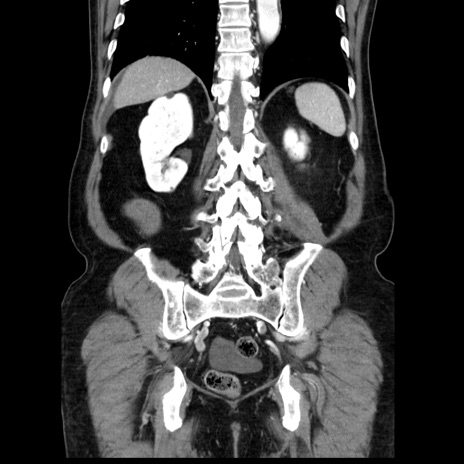

症例30(冠状断像)

【症例】80歳代男性

【主訴】臍周囲痛

【現病歴】約6時間前から臍下部痛が出現。次第に腹部膨隆・背部痛も生じてきたため来院。背部痛の場所は変化しない。

【既往歴】腎盂腎炎

【身体所見】意識清明、BT 36.3℃、BP  131/87mmHg、P 87bpm、SpO2 100%(RA)、臍周囲自発痛・圧痛あり、反跳痛なし、自発痛部位に一致して板状硬あり、腹部膨隆、腸雑音減弱、CVA tenderness両側陰性。

【データ】WBC 19600、CRP 0.33